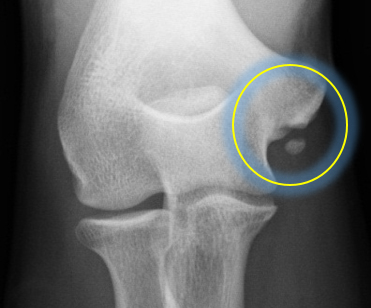

内側側副靭帯(尺側側副靭帯:UCL)は、肘の内側に張る靭帯で、投球動作など肘関節がしなる際にしなりすぎないように働く靭帯です(図1)。近年、プロ野球選手やメージャーリーガーでも多くの選手がUCL損傷を発症し、手術的治療を行ったことが報道されています。初発で靭帯損傷が軽度であれば手術を行わず、リハビリで復帰することも可能ですが、靭帯損傷が高度であれば手術的治療も考慮します。保存療法成績は,42%~84%と報告されています。

当院の調査では、内側上顆に学童期の遺残裂離骨片を有する症例(図2:リスク2.6倍),MRIでの完全損傷(図3:リスク4.6倍)を有する症例が手術を要するリスクが高まることが分かっています。詳細な評価に基づく診断を行い,3ヶ月以上のリハビリテーションを主体とした保存療法を行っても競技復帰が達成できない場合は手術療法を考慮します。手術を行う条件として,選手が競技復帰・継続を強く希望することが必須となります。